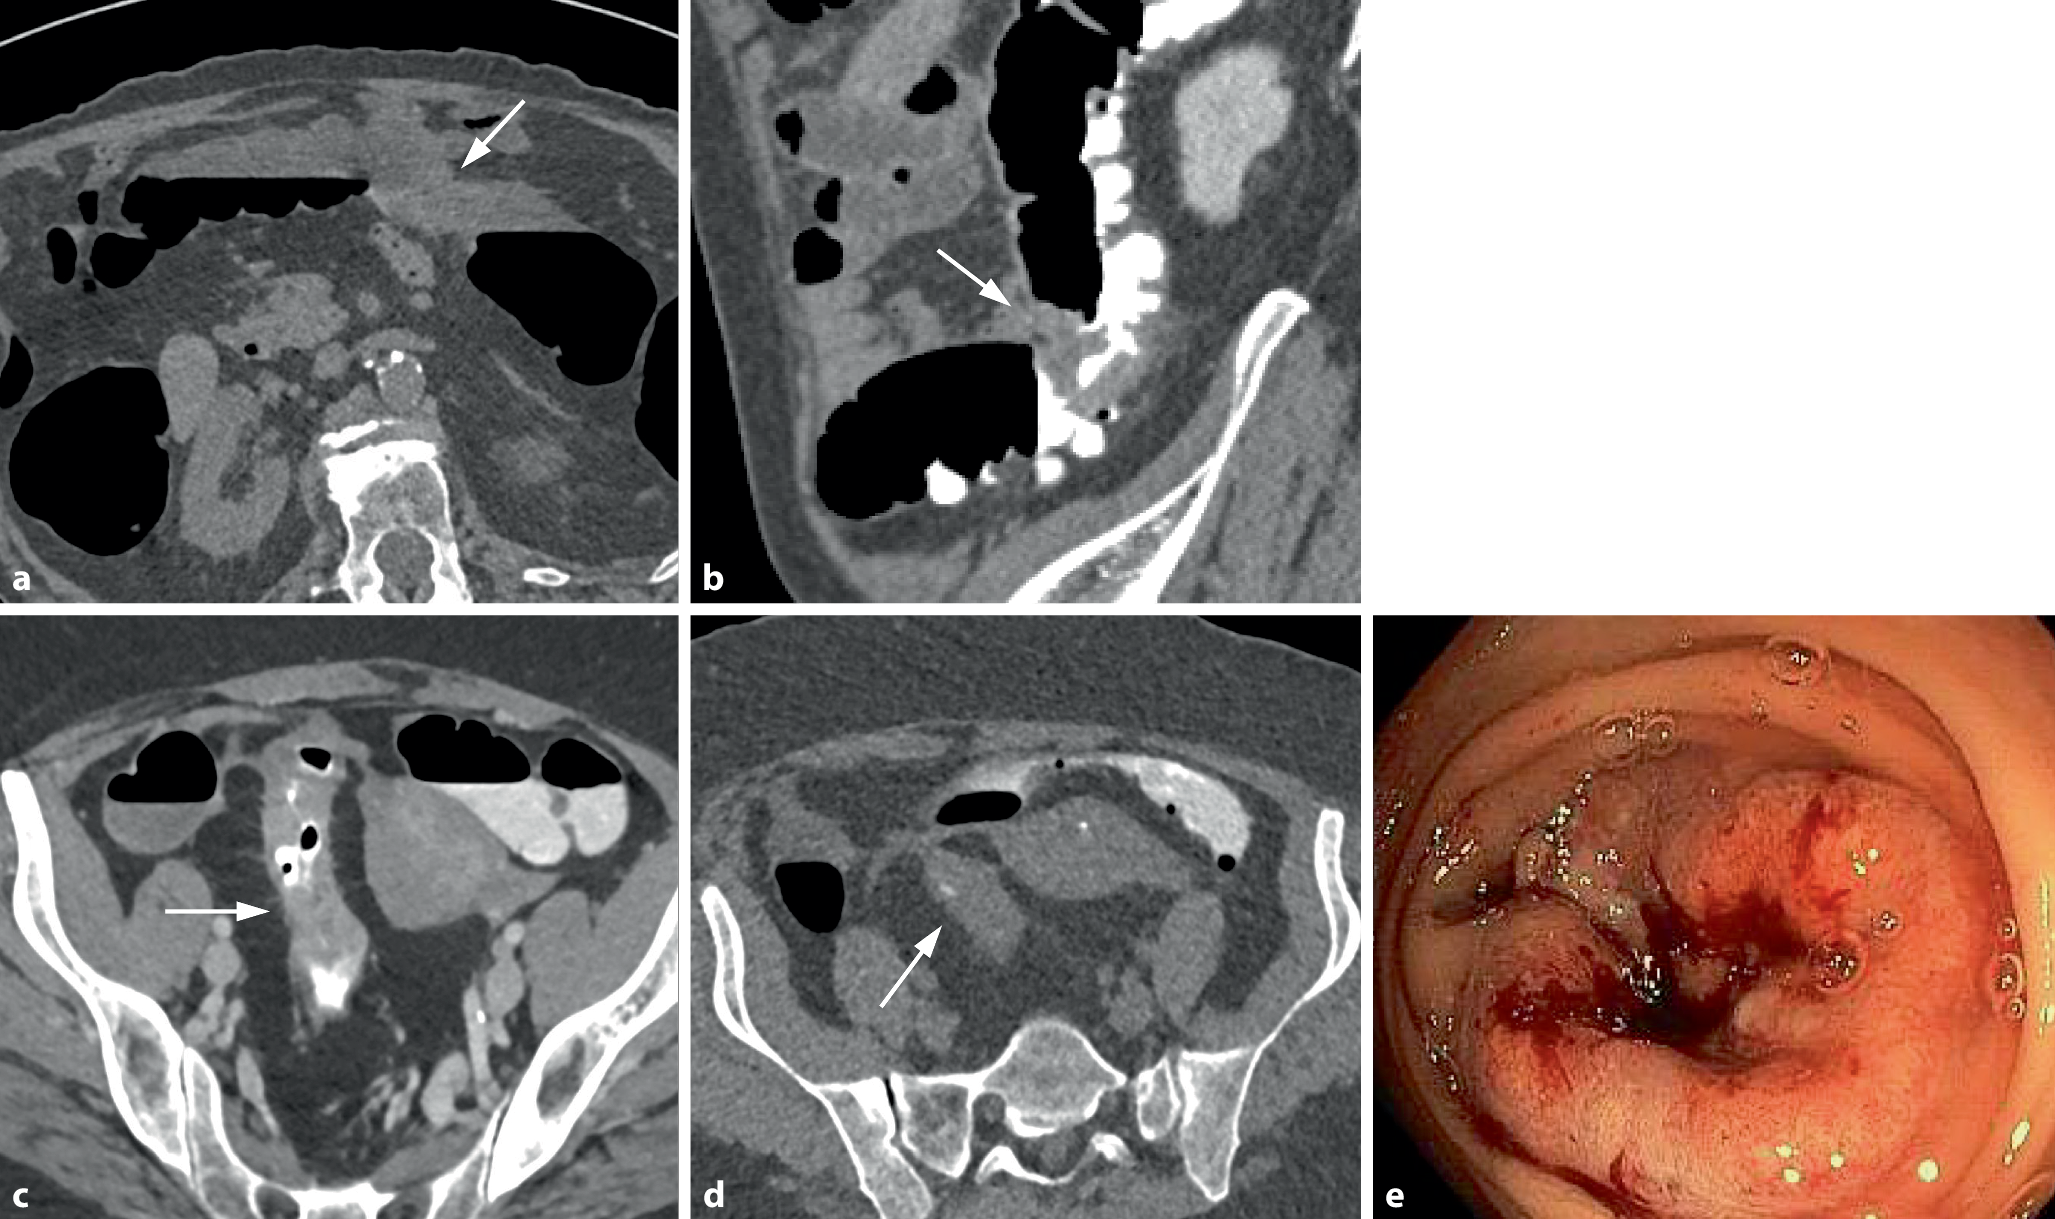

Bei zirkulär stenosierenden Tumoren umfasst die tumoröse Darmwandverbreiterung die gesamte Zirkumferenz des Darms (Abb. 2). Auf endoluminalen 3D-Ansichten erscheinen diese Karzinome meist als zirkuläre symmetrisch oder exzentrisch stenosierende Wandverbreiterungen. Das Ausmaß der Einengung des Darmlumens variiert und kann so ausgeprägt sein, dass diese Tumoren endoskopisch nicht passierbar sind.

Abb. 2

Zirkulär stenosierendes Karzinom im Colon ascendens bei inkompletter Koloskopie aufgrund einer Dickdarmelongation. a Die endoluminale 3D-Ansicht zeigt eine zirkulär stenosierende Raumforderung mit irregulärer Oberfläche und Schulterformation (Pfeil). b Das axiale 2D-Bild in Rückenlage zeigt die zirkuläre weichteildichte Wandverbreiterung (Pfeil). Es besteht eine unregelmäßige äußere Begrenzung mit nodulären Tumorinfiltrationen in das perikolische Fettgewebe sowie Fat Stranding als Zeichen der Wandüberschreitung (histologisch pT 3). c In der koronalen 2D-Ansicht ist die kurzstreckige weichteildichte tumoröse Wandverbreiterung mit Schulterformation (Pfeil) erkennbar. d In der globalen 3D-Ansicht zeigt sich die exakte Tumorlokalisation im Colon ascendens und der typische „Apple-core-Aspekt“ (Pfeil). Das Karzinom liegt bei 180 cm oberhalb des anorektalen Übergangs. Die Dickdarmgesamtlänge beträgt 220 cm

Bild vergrößern

Symptomatische Tumoren sind hingegen größer und bereits invasiver. Sie weisen häufiger eine zirkuläre Morphologie auf und engen das Darmlumen in größerem Ausmaß ein (Abb. 2; [32]).